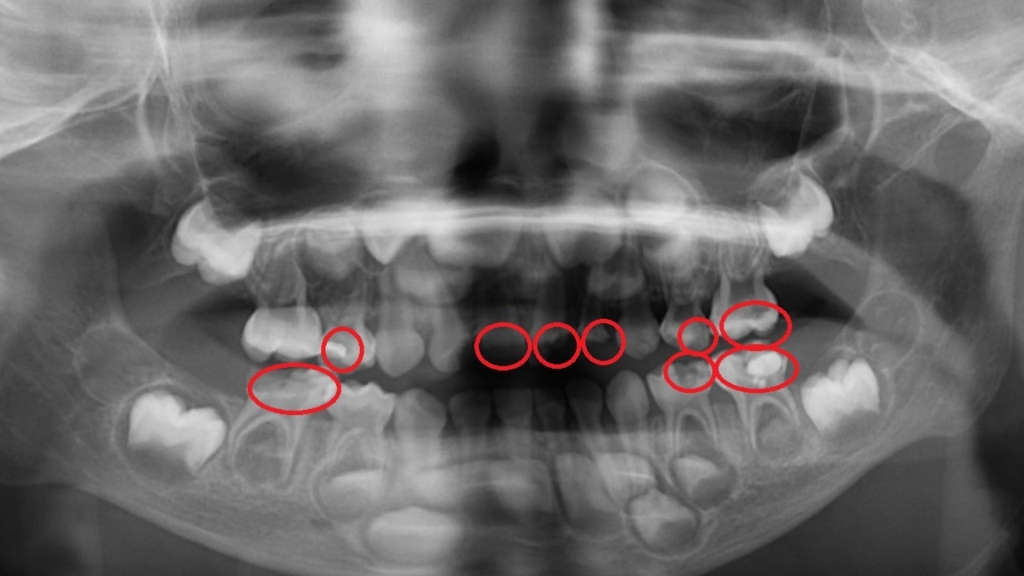

5歲小宏在幼兒園定期接受塗氟和口腔檢查,均未察覺異狀,但日前直到卻出現牙痛情形,而且臉頰腫脹相當不舒服,因此被父母帶至就醫。台北慈濟醫院兒童牙科醫師陳默檢查發現,小宏罹患嚴重齲齒並已引發蜂窩性組織炎,雖然積極治療,但最後不得不拔除4顆已無法補救的乳牙。醫師陳默對此表示,學校塗氟雖有幫助,但無法取代完整的牙科檢查與X光診斷,家長應該自孩子長牙後就要定期帶至牙科門診檢查,勿等蛀牙惡化才就醫。

4.定期至牙科檢查:雖然學校會定期塗氟,但礙於環境及燈光,執行醫師未必每次都能清楚檢查牙齒狀況,因此即使孩子沒有牙痛或明顯異常,也應至少每半年至專業的兒童牙科進行檢查,以利及早發現肉眼難以察覺的齲齒